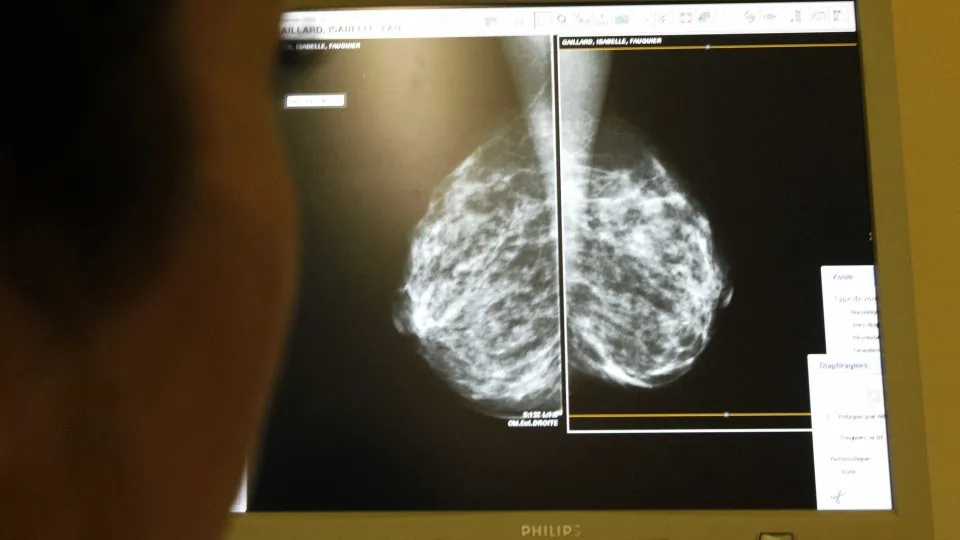

Fora do sistema digestório, o câncer de pulmão e de órgãos do sistema respiratório é o mais letal, com 22.853 mortes registradas ao longo do ano. Já os tipos mais incidentes variam conforme o gênero: o câncer de mama é o mais comum entre as mulheres, enquanto o de próstata lidera entre os homens.

Foto: Reuters